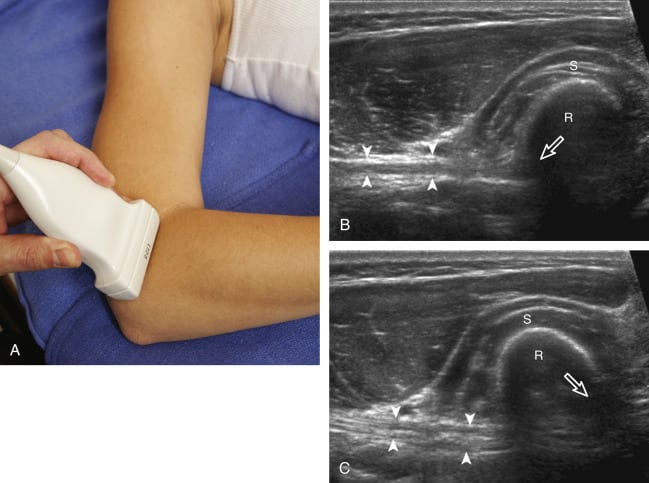

Musculoskeletal ultrasound is a common, affordable, harmless, and painless modality used by radiologists to generate real-time images of muscles, tendons, ligaments, nerves, joints, and cartilage.

MSK Ultrasound can help to identify a range of acute and chronic inflammatory or injuries related conditions such as tendonitis, bursitis, injures, trapped nerves, arthritis, tears, joint problems, and masses such as tumours or cysts.

- ✔ Real-time visualisation of tendons, ligaments, muscles, bursae and fluid

- ✔ Ability to assess movement and pain dynamically during scanning